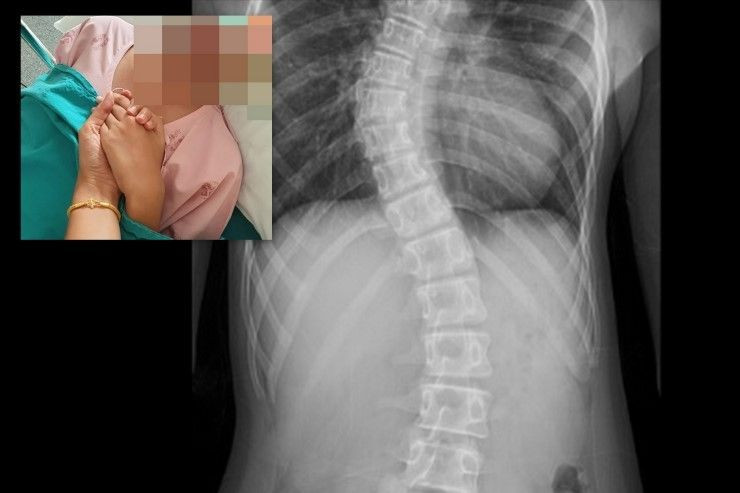

วันที่ 31 ต.ค.2561 ผลเอกซเรย์ครั้งที่ 2 กระดูกสันหลังคดเพิ่มเป็น 30 องศา ต่อมาจากนั้นอีก 6 เดือน ตรวจพบว่ากระดูกคดเพิ่มเป็น 40 องศา แพทย์ลงความเห็นอาจจะต้องใส่เสื้อเกราะดามไว้หรือผ่าตัด แต่ที่โรงพยาบาลไม่สามารถผ่าตัดได้จากเครื่องมือที่ไม่พร้อมและที่สำคัญผู้ป่วยยังไม่มีประจำเดือน ทำให้ร่างกายของผู้ป่วยยังไม่หยุดการเจริญเติบโต การผ่าตัดในตอนนี้จึงอาจจะก่อปัญหาตามมาได้ ในระหว่างที่ส่งตัวเพื่อรักษาเพียง 2 สัปดาห์ เอกซเรย์พบว่า กระดูกหลังคด 54 องศา และมีลักษณะเห็นได้ชัดเป็นรูปตัว ‘S’ จึงจำเป็นต้องผ่าตัดเป็นการด่วน แต่เด็กส่วนมากจะมาผ่าช่วงปิดเทอม ซึ่งคิวยาวมากต้องรอจึงขอคิวที่ไม่ตรงกับช่วงปิดเทอมเพราะถ้ายิ่งรอมันมีโอกาสยิ่งคด และการทำ MRI เองก็มีคิวที่แน่นเช่นเดียวกัน

วันที่ 28 พ.ค. หลังจากการผ่าตัดมีอาการเสียเลือดเยอะมากต้องให้ออกซิเจน และมีอาการปวดหลังตลอด แพทย์จึงให้ยาแก้ปวดทางแขนข้างขวา แขนซ้ายเจาะสายน้ำเกลือ ข้างหลังมีสายระบายเลือด ต้องใส่ท่อปัสสาวะ แต่โดยรวมอาการดีขึ้นมาก แผลไม่บวมและไม่มีเลือดซึม โดยในวันที่ 2-6 ไม่สามารถลุกจากเตียงได้ คุณแม่ต้องคอยช่วยทุกอย่างทั้งเช็ดตัว เปลี่ยนผ้า แปรงฟัน ป้อนอาหาร หลังจากครบ 1 อาทิตย์ แพทย์อนุญาติให้ลุกขึ้นนั่งได้เป็นครั้งแรกและทำการตัดเสื้อเกราะและสวมใส่เพื่อประคองหลัง ซึ่งจะต้องใส่เสื้อเกราะประคองไว้ตลอดช่วง 3 เดือนแรกหลังผ่าตัด ยกเว้นตอนนอน ก่อนอนุญาตให้กลับบ้านได้ในวันรุ่งขึ้นโดยนัดตรวจแผลติดตามอาการเป็นระยะๆ ต่อไป